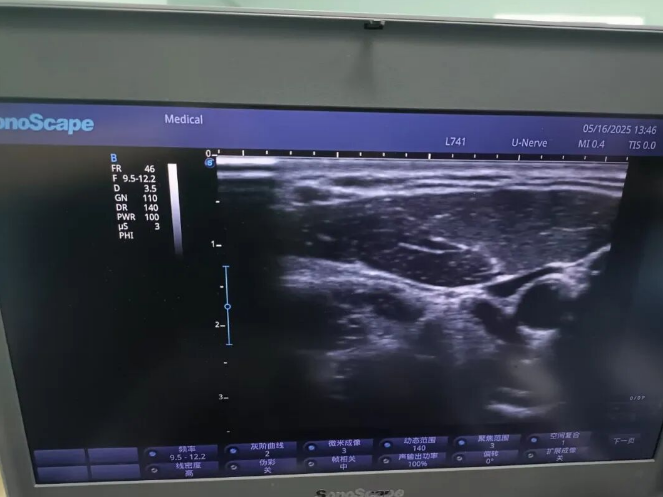

患者为39岁男性,因双侧锁骨骨折需行内固定取出术,但合并长期饮酒史、高血压、肝功能不全及肺部感染,传统全身麻醉风险极高。肝功能异常易致麻醉代谢障碍,肺部感染可能诱发术后呼吸衰竭。面对患者“全麻禁忌”的困境,麻醉科选择超声可视化双侧颈神经通路阻滞技术,精准定位目标神经,避免损伤周围血管与脏器,以最小创伤实现最佳麻醉效果。

术前麻醉医生凭借娴熟的超声技术,清晰辨识颈部神经与血管走向,将局麻药精准注入目标区域,双侧神经阻滞一次成功。创伤科团队紧密配合,高效完成双侧锁骨内固定取出。术后患者无不适症状,真正实现“精准麻醉、快速康复”。